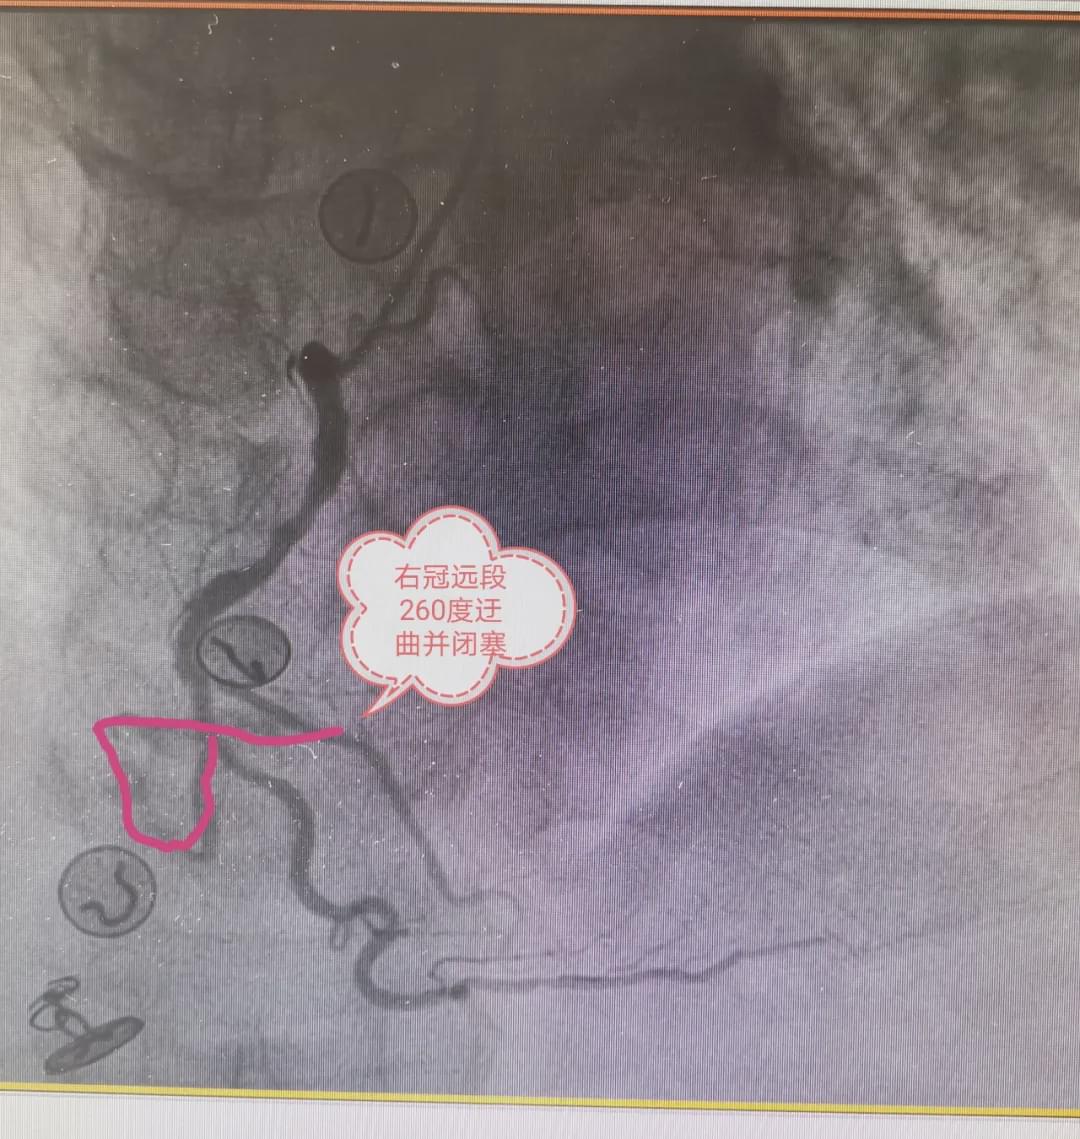

患者进入手术室后,立即给予消毒、心电监护、吸氧,手术医生开始穿刺、顺利造影完毕,造影显示患者严重三支病变,根据心电图结果考虑此次疾病为右冠状动脉中段完全闭塞所致,立即为患者开通血管,在导丝通过时才发现闭塞部位血管严重迂曲、260°成角畸形,应用球囊支撑,导丝勉强到达远端,造影显示不清楚,无法判断导丝在真假腔内,如果进入假腔,行支架术,将导致冠脉夹层,手术失败,患者发生猝死风险极高,丁水印主任立即下指令,应用血管内超声明确远端导丝的具体位置,介入手术室护士周程昊立即启动仪器,超声显示远端导丝穿入假腔后又进入真腔,在血管内超声的引导下,及时调整了导丝的位置,很快进行球囊扩张及支架植入术,患者右冠状动脉血流通畅,远端血管粗大,患者症状很快改善,生命体征稳定,此时患者从进入医院大门到血管开通,仅用时38分钟!